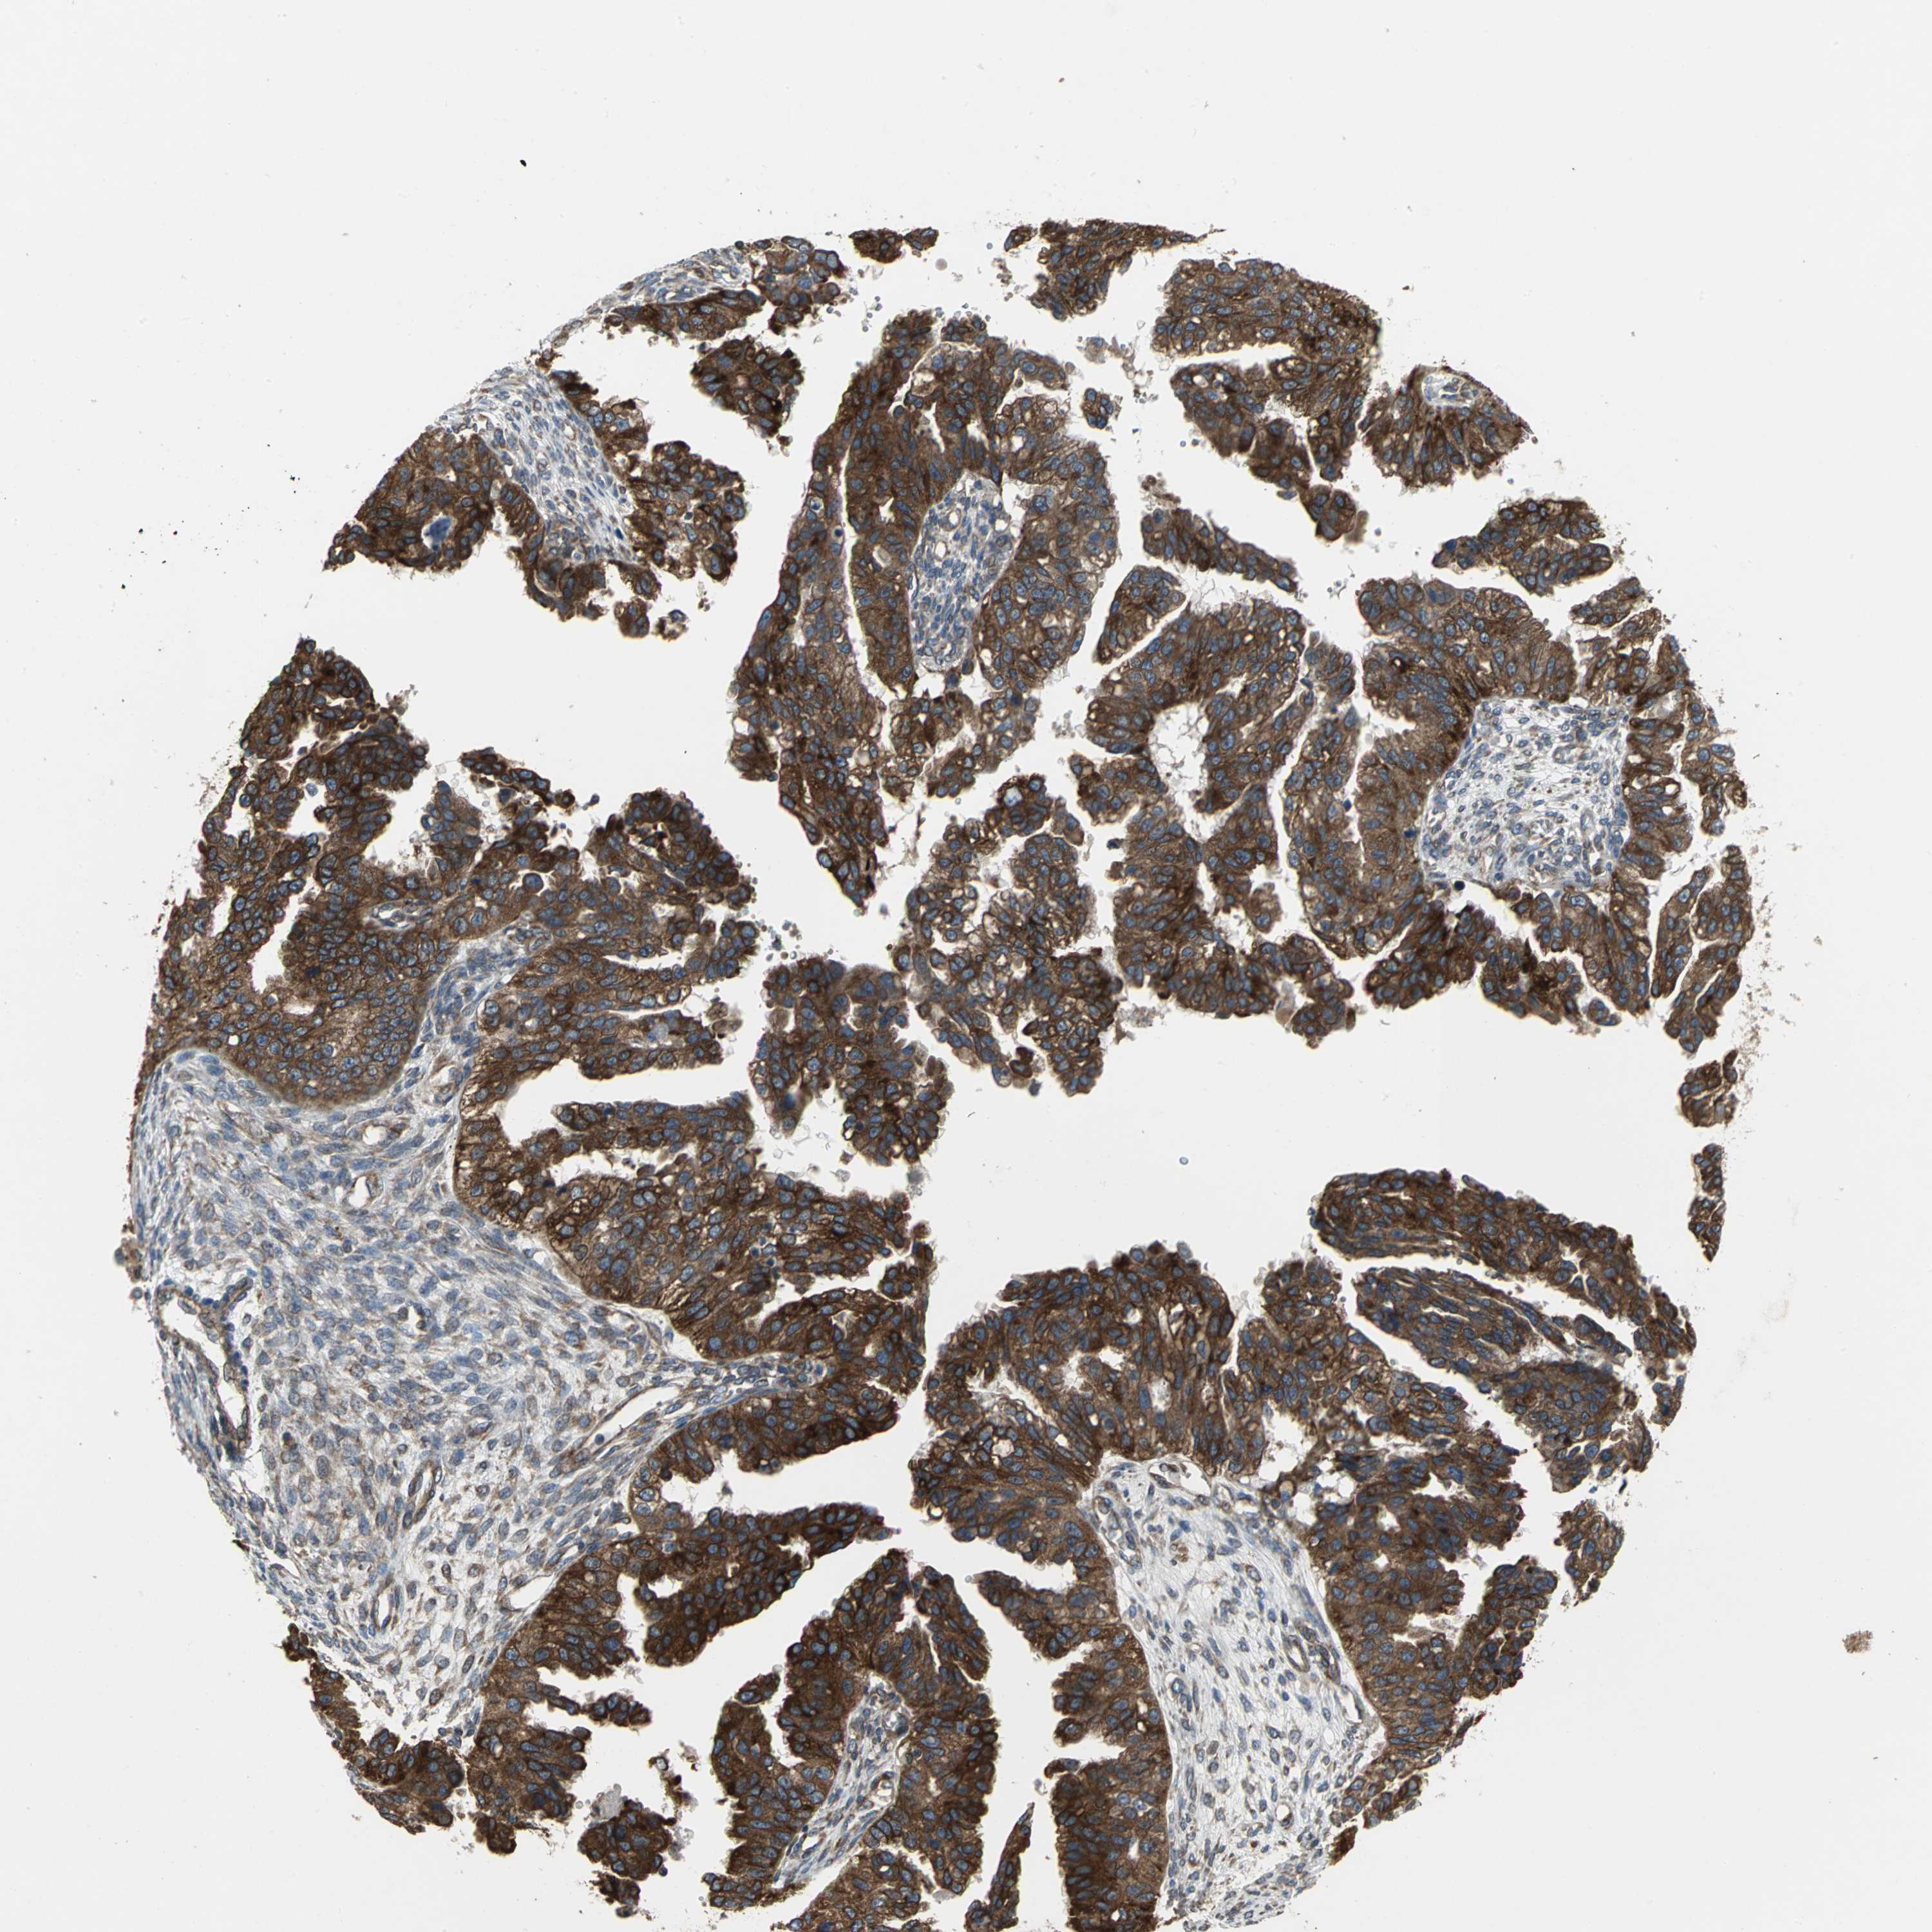

OVARIAN CANCER - Protein expressioni

A mouse-over function shows sample information and annotation data. Click on an image to view it in a full screen mode. Samples can be filtered based on level of antibody staining by selecting one or several of the following categories: high, medium, low and not detected. The assay and annotation is described here.

Note that samples used for immunohistochemistry by the Human Protein Atlas do not correspond to samples in the TCGA dataset.

Antibody stainingi

Antibody staining in the annotated cell types in the current human tissue is reported as not detected, low, medium, or high, based on conventional immunohistochemistry profiling in selected tissues. This score is based on the combination of the staining intensity and fraction of stained cells.

Each image is clickable and will lead to virtual microscopy that enables deeper exploration of all samples and also displays staining intensity scores, fraction scores and subcellular localization as well as patient and tissue information for each sample.

Antibody HPA005480

Cystadenocarcinoma, serous, NOS

Carcinoma, endometroid

Carcinoma, NOS

Cystadenocarcinoma, mucinous, NOS